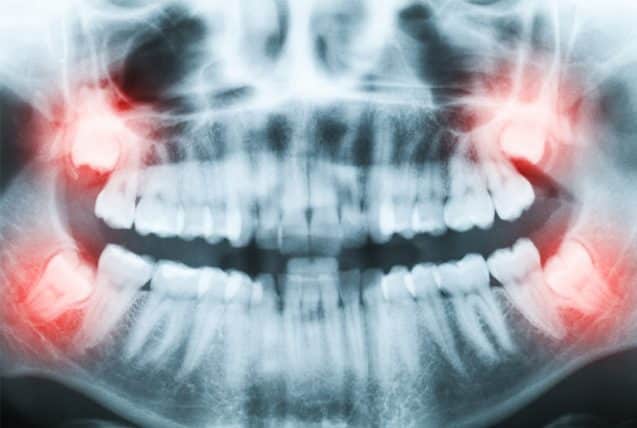

Let's say you have dental insurance and you plan to use it for your 3rd molar removal. Why are wisdom teeth removed? Does dental insurance cover tooth extraction cost? There are other affordable ways to get your wisdom teeth removed without insurance. Without insurance, the cost of wisdom tooth removal ranges from $720 to $4,000. If you need all four wisdom teeth removed, this comes to $2,564. During the initial process, the cost without insurance would be about $300. If you are without insurance (no insurance) we have payment plans available that should.

Additional costs of wisdom tooth removal. If it's deemed medically necessary. How much does wisdom teeth removal cost? Wisdom teeth removal without insurance might be somewhat daunting when you have four teeth that are just waiting to be removed. In some cases, dental insurance plans only a pay a maximum of $1,000 to $1,500. The average insurance cover about $1,500 towards the cost of wisdom teeth removal. Upper wisdom teeth removal is usually more straightforward than lower and therefore may cost less. If you need all four wisdom teeth removed, this comes to $2,564. Dental insurance can be costly. But if you have a dental insurance, then it may cover 15 to 50 percent of the total surgical cost. The cost to remove impacted wisdom teeth without dental insurance is less than you think healthcare plans cover this medically necessary surgery. Let's say you have dental insurance and you plan to use it for your 3rd molar removal. This selection of excellent dentists makes the cost of wisdom teeth removal without insurance easier to handle with payment plans that require little or no interest.

Impacted teeth will usually be much more costly, with the cost you can then find out about the cost of wisdom teeth removal with or without insurance, and then decide which location is best for you. How much does wisdom teeth removal cost? The cost of wisdom teeth removal depends on a variety of factors, including whether or not you have insurance and how many wisdom teeth need to be removed. Insurance coverage for wisdom teeth removal depends on your dental insurance plan. Your insurance provider can be a big helping hand if you're struggling to pay for dental procedures. Without dental insurance, you can expect wisdom teeth removal costs to be around $200 to $700 per tooth. Wisdom teeth removal cost based on the type of extraction. The cost to remove impacted wisdom teeth without dental insurance is less than you think healthcare plans cover this medically necessary surgery. Getting wisdom teeth removed without insurance isn't an affordable option for most people. Cost is about $1,600 for 4 wisdom teeth. Just as importantly, what is the cost of wisdom teeth removal with no insurance? Insurance generally covers around 80 percent of the cost for extraction. During the initial process, the cost without insurance would be about $300.

When should you remove wisdom teeth? Almost all dental insurance schemes cover up to 40 to 60 percent of the total cost of. Average cost of wisdom tooth extraction without insurance. The cost of wisdom teeth removal depends on a variety of factors, including whether or not you have insurance and how many wisdom teeth need to be removed. Your insurance provider can be a big helping hand if you're struggling to pay for dental procedures. If you are without insurance (no insurance) we have payment plans available that should. In some cases, dental insurance plans only a pay a maximum of $1,000 to $1,500. That's why when you're looking into, you'll most likely find a variety of rates — however a tooth that is easy to get rid of can cost just $75. While impacted wisdom teeth cost upwards of $600. Cost is about $1,600 for 4 wisdom teeth. Why is wisdom tooth removal so costly, exhausting, and risky? Upper wisdom teeth removal is usually more straightforward than lower and therefore may cost less. During the initial process, the cost without insurance would be about $300.